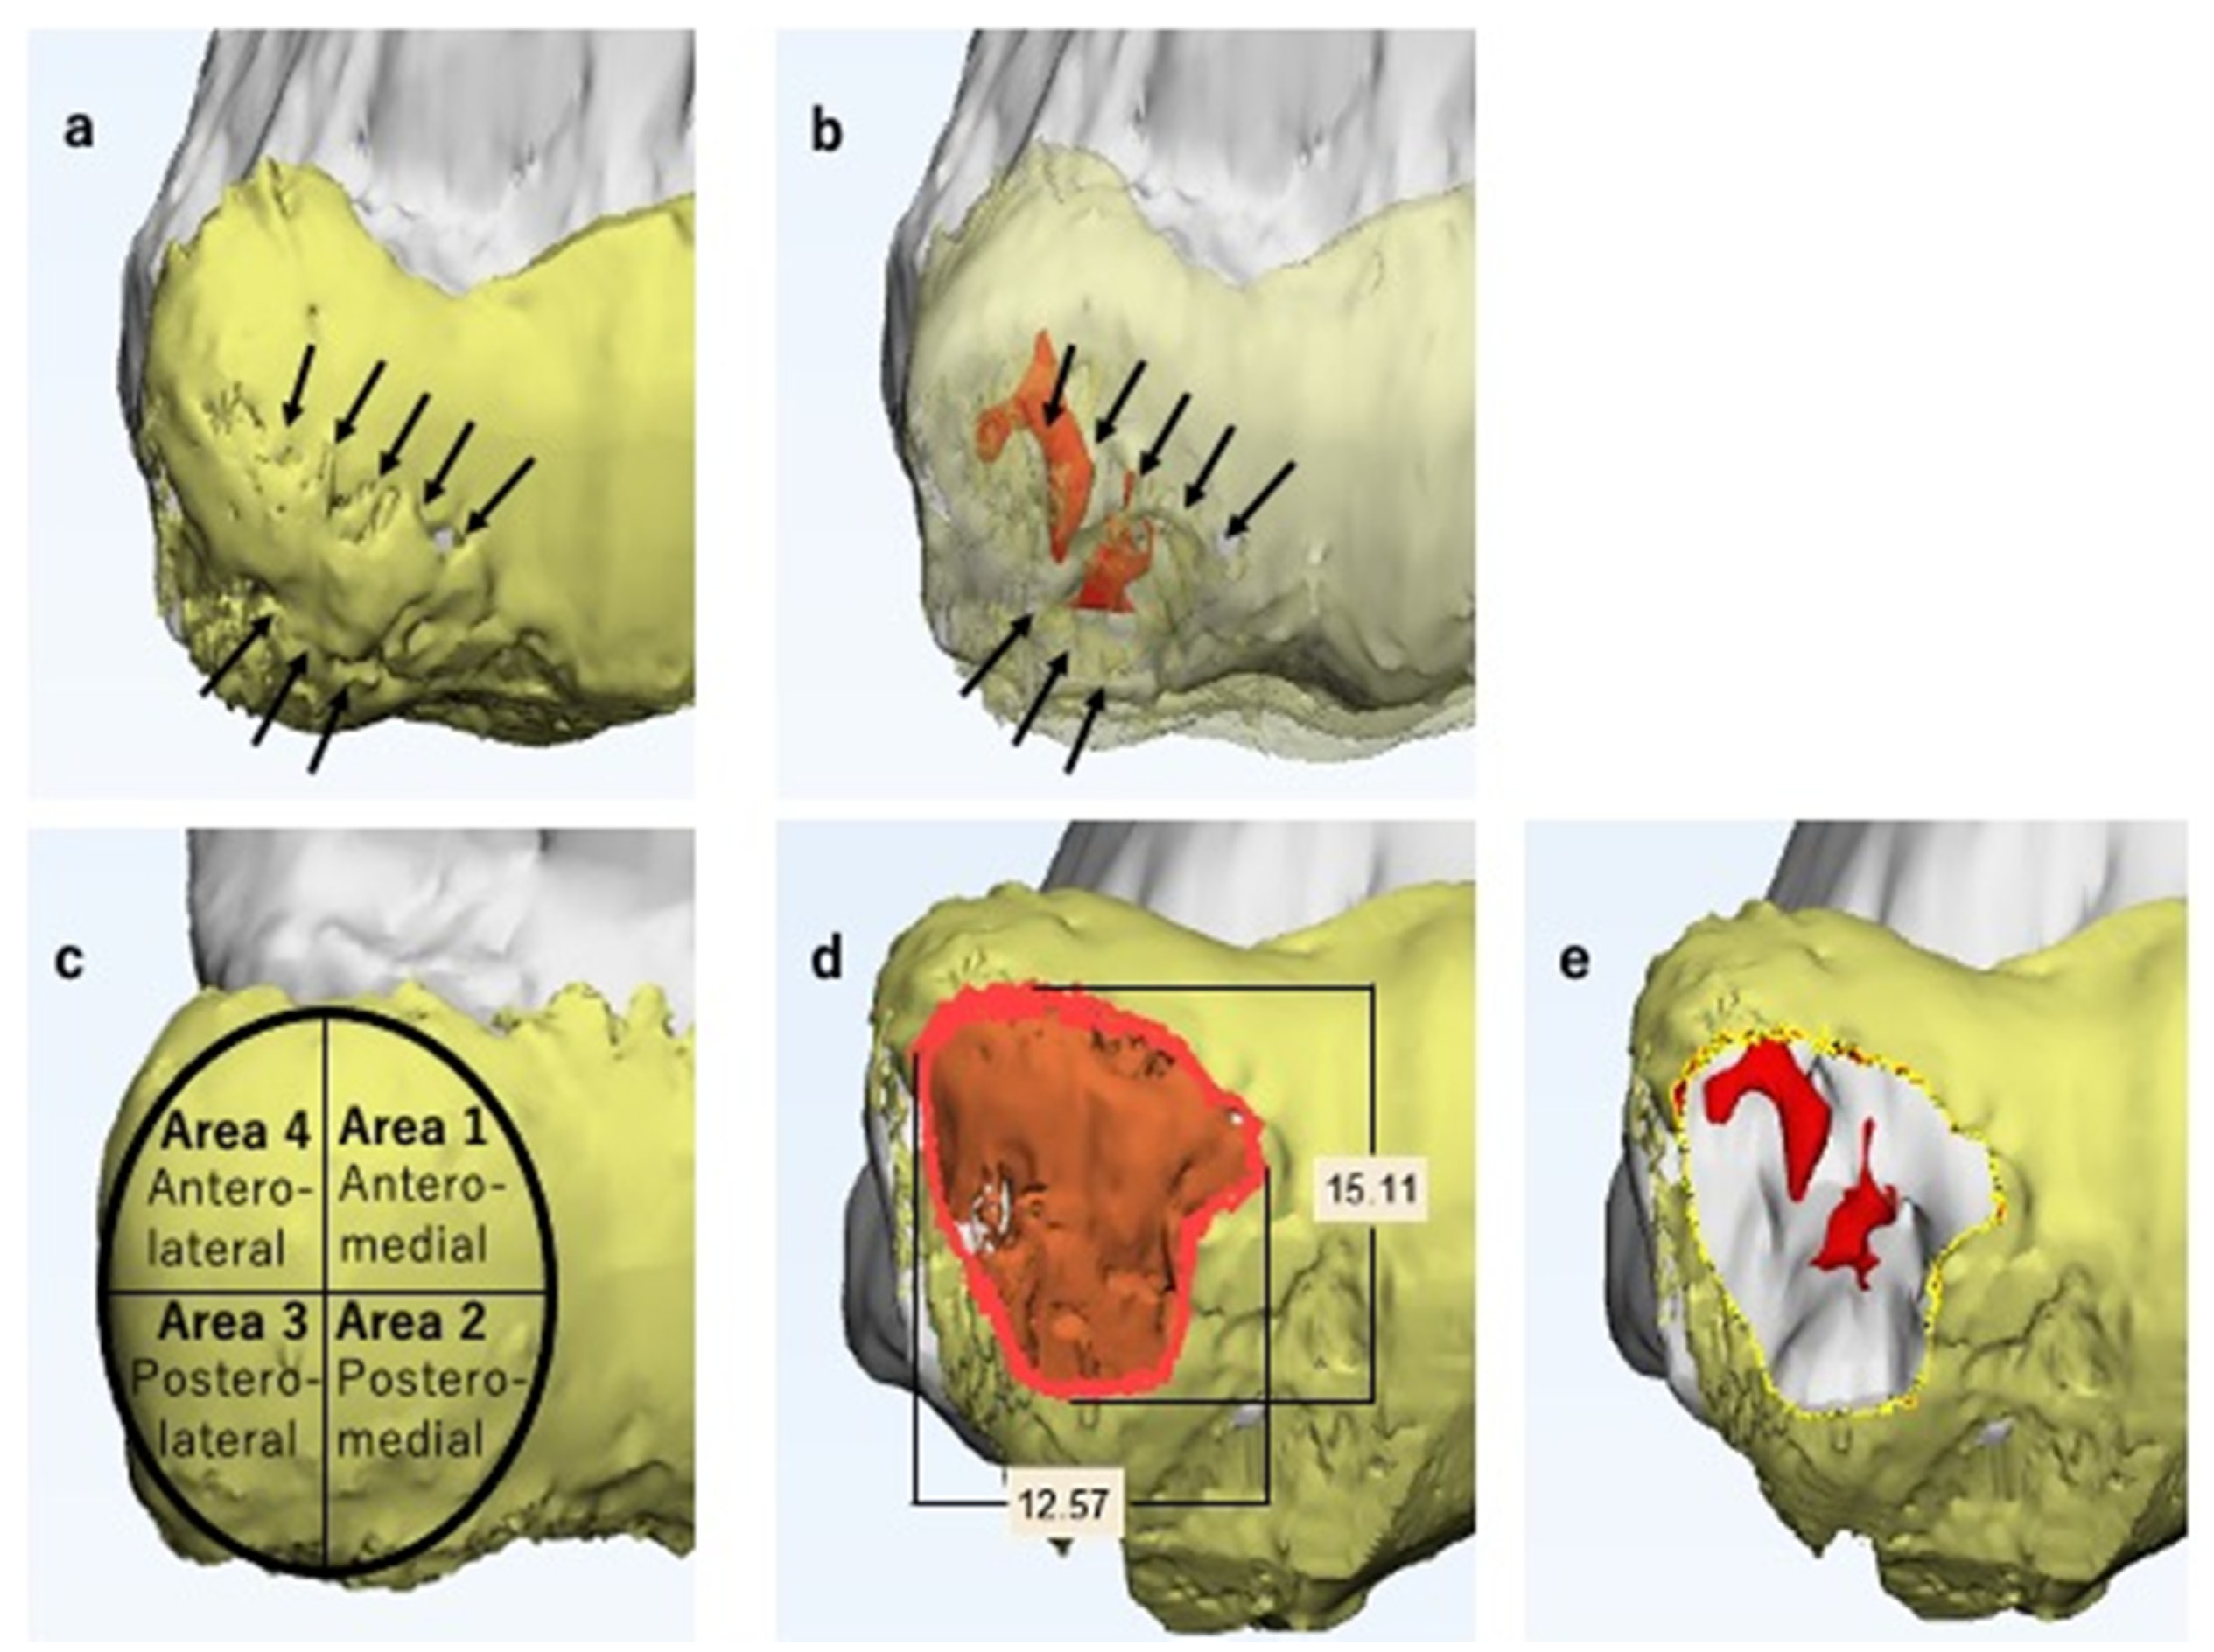

2.5. Lesion Evaluation Using MCFIs

2.6. Surgical Simulation

3.3. Surgical Simulation